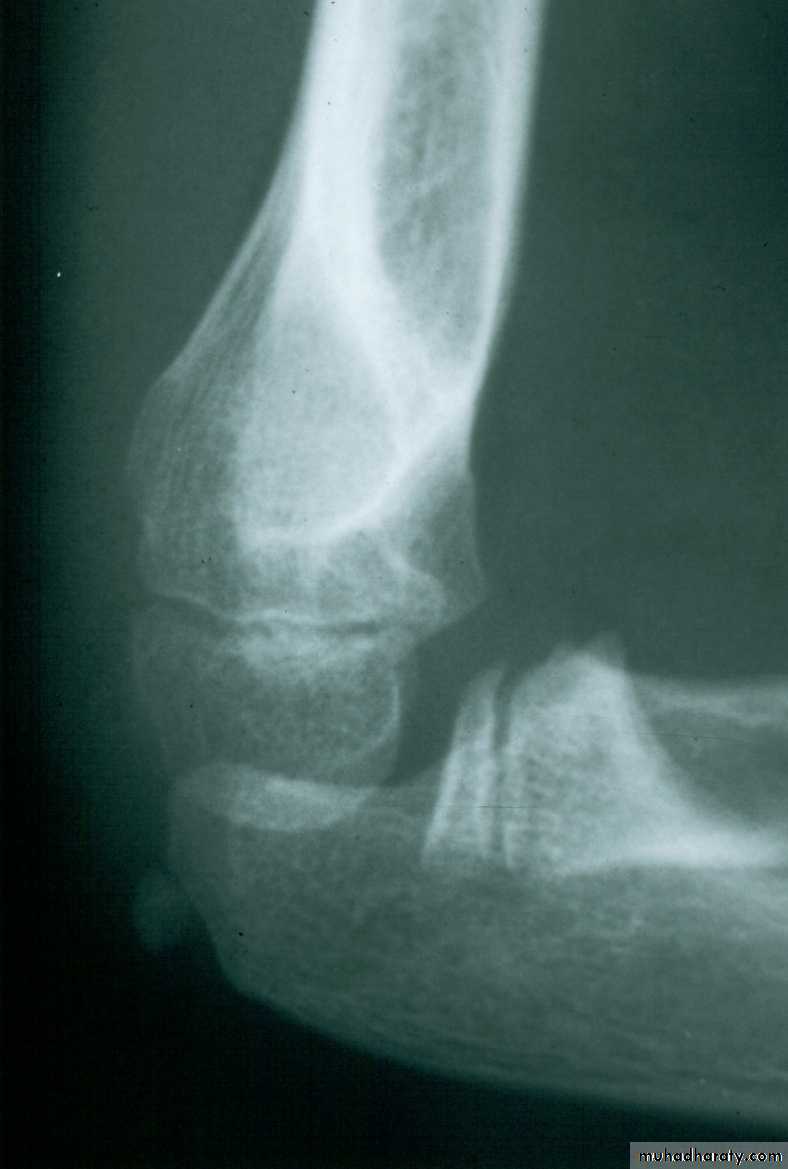

This fracture

was irreducibleby closed

manipulation.

Injury film

Post-reduction

Gap persists

6 weeks3 months

Gap has remodeled

X-ray evidence of this periosteal interposition

often is demonstrated as a gap in many fractures

Gap with interposed

periosteum

Mind the Gap!